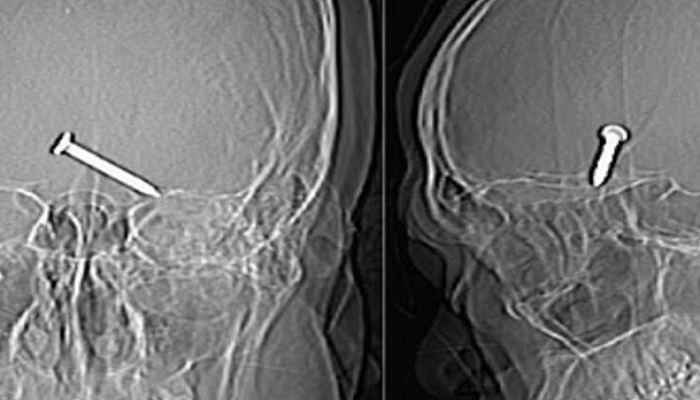

Fue trasladado de emergencia al hospital Sultanah Bahiyah de

la ciudad de Alor Setar, con el ojo hinchado y sangrando. Los médicos al

tomarle radiografías a su cráneo comprobaron que el clavo había embestido el

lóbulo frontal del cerebro, área crucial del órgano encargada de las funciones

motoras y cognitivas.